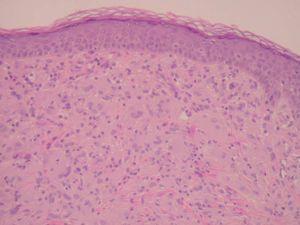

A las 38 semanas del tratamiento la paciente presentó varias lesiones papulosas semiesféricas eritemato-amarillentas en mejilla derecha (zona preauricular) de pocos milímetros de diámetro, muy bien definidas y tacto sólido (fig. 4). Se tomó una de las lesiones para estudio histopatológico, que mostró un infiltrado difuso en dermis papilar y reticular superficial, constituido en su mayor parte por histiocitos de citoplasma amplio, basófilo, con xantomización ocasional (fig. 5). Se observaban algunos linfocitos y eosinófilos entremezclados. El estudio inmunohistoquímico de estas células mostró un perfil macrofágico CD68+ , S-100 y CD1a (fig. 6). Por todo ello, se llegó al diagnóstico de xantogranuloma juvenil. Durante los meses siguientes al final del tratamiento de la HCL no se observaron lesiones de dicha enfermedad en la piel ni a otros niveles, pero siguieron apareciendo pequeñas pápulas compatibles con XGJ en cara, tronco y miembros.

Fig. 5.—Infiltrado dérmico por células histiocitarias xantomizadas formando células gigantes tipo Touton (hematoxilina-eosina, ×60).